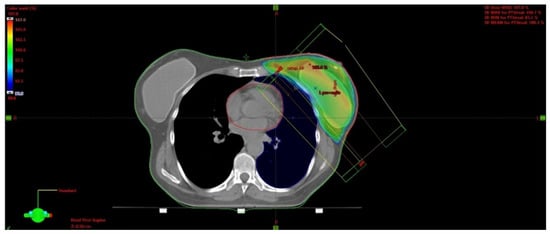

5.3. Postoperative Partial Breast Irradiation

This is a non-invasive technique with advantages over brachytherapy and intraoperative radiotherapy that include ease of accessibility and potentially a better dose homogeneity. In contrast with WBI, PBI is based upon irradiating a limited volume of tissue (Figure 2). External postoperative radiotherapy has many advantages in comparison with intraoperative procedures. The treatment is initiated with knowledge of the definite and complete histology, including the immunohistochemistry, and, in comparison with brachytherapy, it is less dependent upon the individual technical quality of the treatment’s execution.

Figure 2.

3D visualization of external beam PBI technique from different viewing angles, delineation and dose distribution: heart—red, left ventricle and left anterior descending artery—white, left breast—orange, left lung—blue. Photon dose distribution produced by LINAC is presented by the color distribution: 95—107% of prescribed dose; 40 Gy/15 fractions.